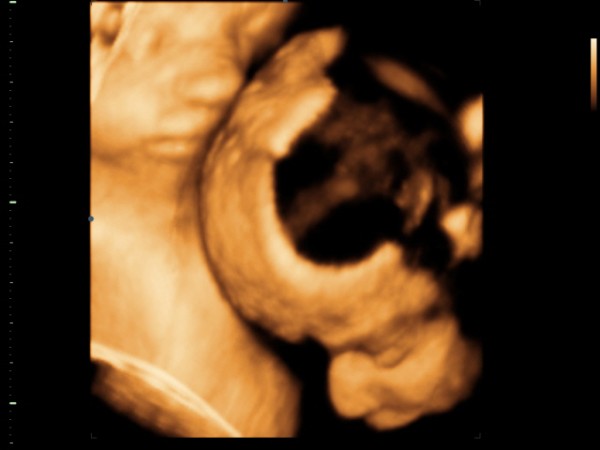

Uh: Hát már a végén voltunk, ezért kissé gyorsabban folyt a vizsgálat, mint Katicánál, de azért nagyon szuper volt. Láthattuk a babók arcát ÉÉÉÉÉÉÉÉÉÉÉÉÉÉÉÉéééééééééés sok újat megtudtunk:

- mindkét baba fejvégű már, tehát szülhetek természetes módon :D

- két lepény van, az eddig tudott egy helyett, ami nagyon jó - így mondjuk nem tudni, hogy egy vagy két petéjűek e

- de továbbra is mindketten fiúk :)

Méreteket sajna nem mértek, egy angol hölgy vizsgált, és a placentás dolog elmagyarázásához is kellett egy doki, aki roppant kedves volt :)

A babák most úgy fekszenek, hogy a nagyobb baba (Gergő) bal oldalon van, kissé lentebb, és kisebb baba (Bálint) búbja az ő mellkasán :) Inkább háttal a pocakomnak vannak, a gerincem felé fordulva, úh a nőci látta mennyire szenvedek háton, mondta hogy oldalra is fordulhatok. Jobb is volt, mert kezdtem begörcsölni.

Na és a képek mellett vannak kis videók is a cd-n :) bár van ami kétszer is megvan, de így is olyan jó :)

1. Gergő arc

2. Ketten együtt

3. Bálint arc (a szája elé sajnos belógott a köldökzsinór)